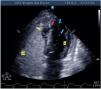

Mujer de 67 años en shock cardiogénico tras infarto de miocardio, con un seudoaneurisma y comunicación interventriculares (CIV): disposición oblicua, medial-anteroseptal a septoapical (fig. 1). Tras la estabilización, se repara con parche bovino. En controles ecocardiográficos objetivamos disfunción del ventrículo derecho (VD) y persistencia de la CIV: con escaso relleno diastólico del seudoaneurisma desde el VD y un predominante relleno sistólico turbulento desde el ventrículo izquierdo (VI), que evacúa al VD mediante 2 jets (Video 1). El salino agitado confirma un discreto relleno del seudoaneurisma desde el VD y rápido lavado del mismo desde el VI, así como el paso de algunas burbujas desde el VD al VI (fig. 2, Video 2). La grave disfunción derecha imposibilitó nueva reparación. Flechas amarilla: seudoaneurisma; flecha verde: CIV; flecha azul: burbujas en el VI; flecha roja: parche. Planos ecográficos: apical 4/5 cámaras y modificado.